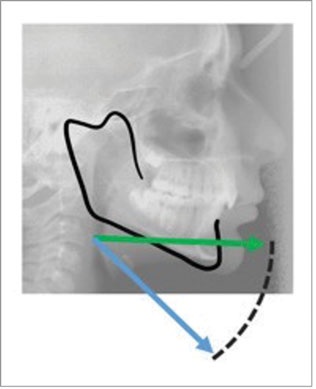

Invisalign treatment with mandibular advancement (Fig. 1) uses integrated precision wings to advance the mandible without the use of interarch elastics. The wings in the lower aligners position the mandible forward by sliding against the wings in the upper aligners. At the same time, the active portions of the aligners straighten the teeth and coordinate the arches to remove interarch interferences and stabilize the sagittal changes. This approach maximizes the horizontal component of the mandibular advancement and minimizes unwanted vertical changes (Fig. 2).

Fig. 2: Horizontal mandibular development (green arrow) has a greater amount of sagittal change than mandibular development, which contains a vertical component (blue arrow).